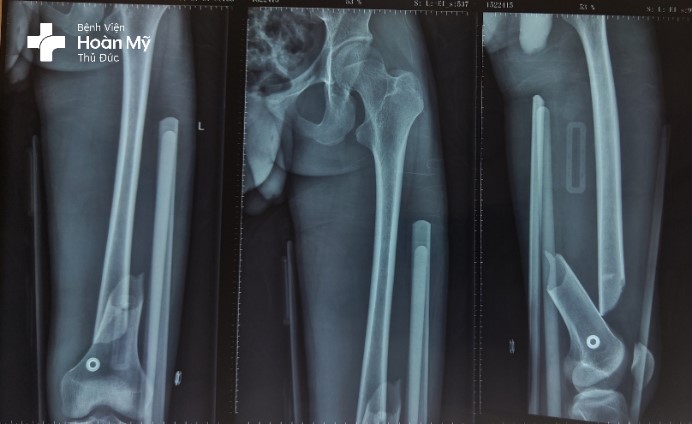

X-quang đùi trái trước mổ gãy 1/3 dưới thân xương đùi trái di lệch nhiều